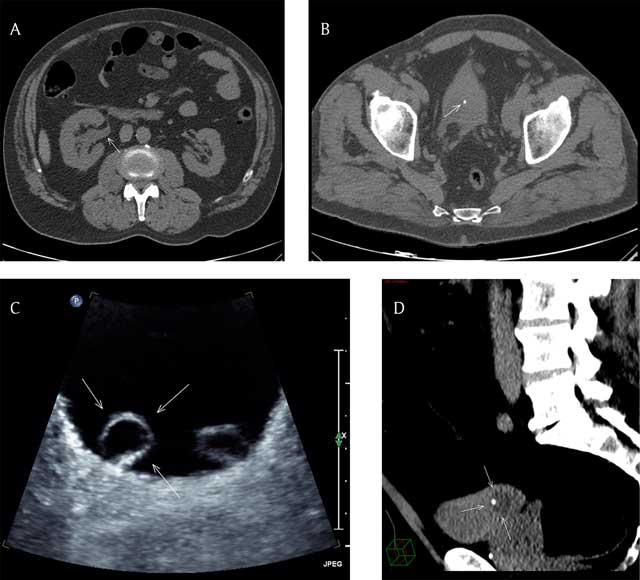

Figure 1

(A) Axial CT scan image (non-contrast) at the level of the abdomen showing right uretero-pyelo-calyceal dilatation (arrow). (B) Axial CT scan image (non-contrast) at the level of the pelvis showing a 3.6 mm hyperdense stone in an almost empty bladder (arrow). (C) Axial US image of the bladder showing bilateral ureterocele, more prominent at right (arrows). (D) Reformatted sagittal CT scan (non-contrast) image with narrow window width of the pelvis showing the urine filled right ureterocele with the stone located inside (arrows).